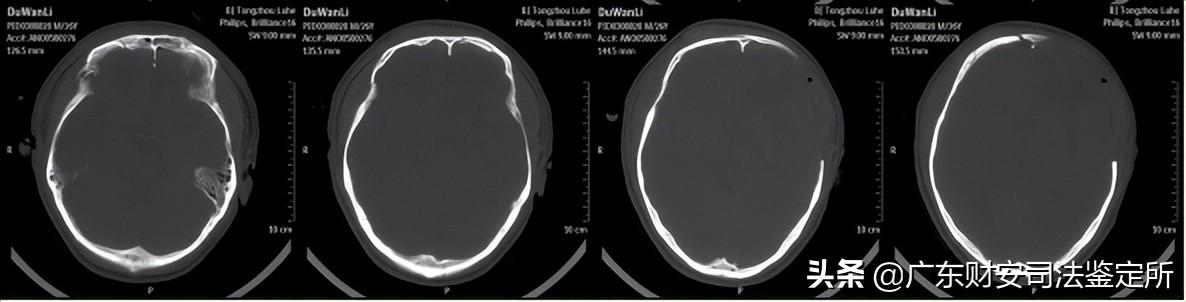

2014-6-16颅面部CT片示:双侧额骨、双眼眶壁、双侧鼻骨等颅面骨多发骨折,颅底骨折,左侧开颅术后,左侧额颞顶部分颅骨缺损,局部脑组织稍向外膨隆,颅内积气,双侧额叶可见少量高密度影,右侧额部可见金属探头,左侧额叶可见不规则大片状低密度区,左侧侧脑室稍受压,局部中线结构稍右偏。(见附件5-A)

2014-6-24颅脑CT片示:右侧额部金属探头已拔除,左侧脑室受压解除,中线结构居中,余基本同前。(见附件5-B)

2014-8-5首次术后颅脑CT片示:左侧开颅术后,额颞部分颅骨缺损,双侧额叶、左侧基底节区、侧脑室旁均可见软化灶、形态不规则,左侧侧脑室轻度扩张,中线结构居中。(见附件5-C)

2014-9-18修补术后复查颅脑CT片示:左侧额颞部颅骨减压修补术后,胼胝体、左侧基底节区可见斑片状低密度灶,双侧额叶可见不规则低密度灶,中线结构居中。(见附件5-D)